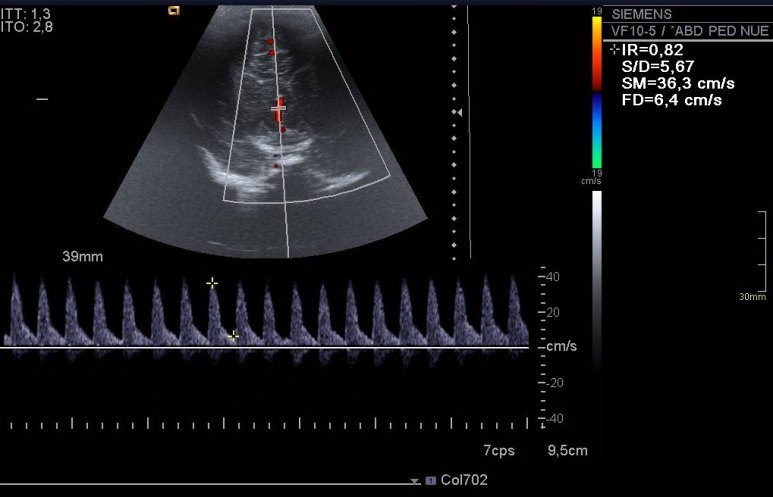

293. Hemorragia Matriz Germinal Grado 1.

Uno de los lugares más especiales para hacer ecografía es en los servicios de neonatología. Hacer una ecografía transfontanelar a un recién nacido es una experiencia inolvidable, es de las pruebas a las que uno le pone siempre especial cariño. Particularmente a mi, me superencanta. Hoy quería subir este caso, muy sencillo. Muy bonito. Me acuerdo de ella, era muy linda.

En el caso de esta pequeña nos pidieron una ecografía de control de una hemorragia de la matriz germinal grado 1 diagnosticada a las pocas horas de nacer.

La hemorragia es la imagen hiperecogénica, homogénea y psudoredondeada del lado derecho. El quiste, redondo e hipoecogénico, del lado izquierdo. No se pudo demostrar una hemorragia en ese lugar.

Pequeña hemorragia matriz germinal lado derecho, grado uno, y pequeño quiste asociado izquierdo indicando reabsorción parcial en ese lugar. Imagen 1.Sistema ventricular de tamaño normal. Imagen 1 a 4.

El índice de resistencia vascular se encontraba en los márgenes normales. Imagen 5.